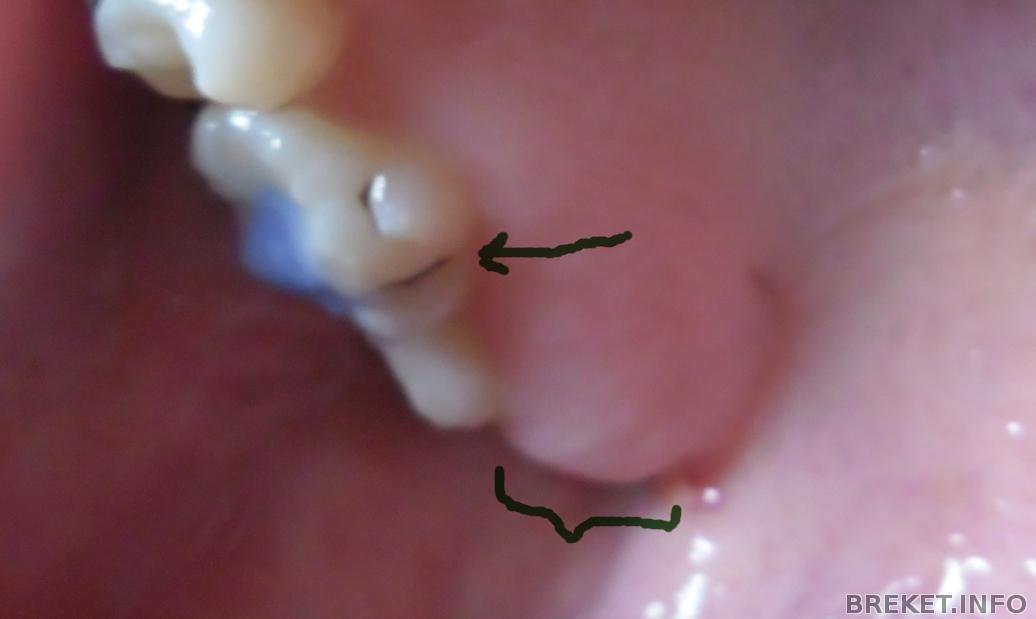

На НЧ установили брекеты через 5 мес. на НЧ отсутствует правая 6-ка. из за чего сместился центр. на фото видно. сейчас ситуация изменилась в худшую сторону. у кого были проблемы с центром? и как решилась эта проблема у вас?

2012-05-01_20.04.25.jpg